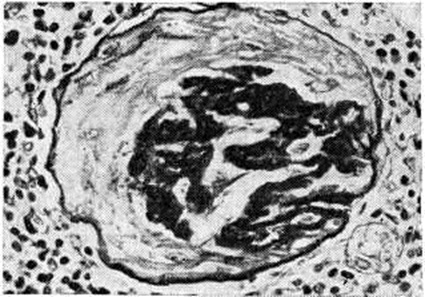

Рис. 2.

Микропрепарат почки при доброкачественной форме нефросклероза: склероз и гиалиноз почечного клубочка, ШИК реакция; × 750.